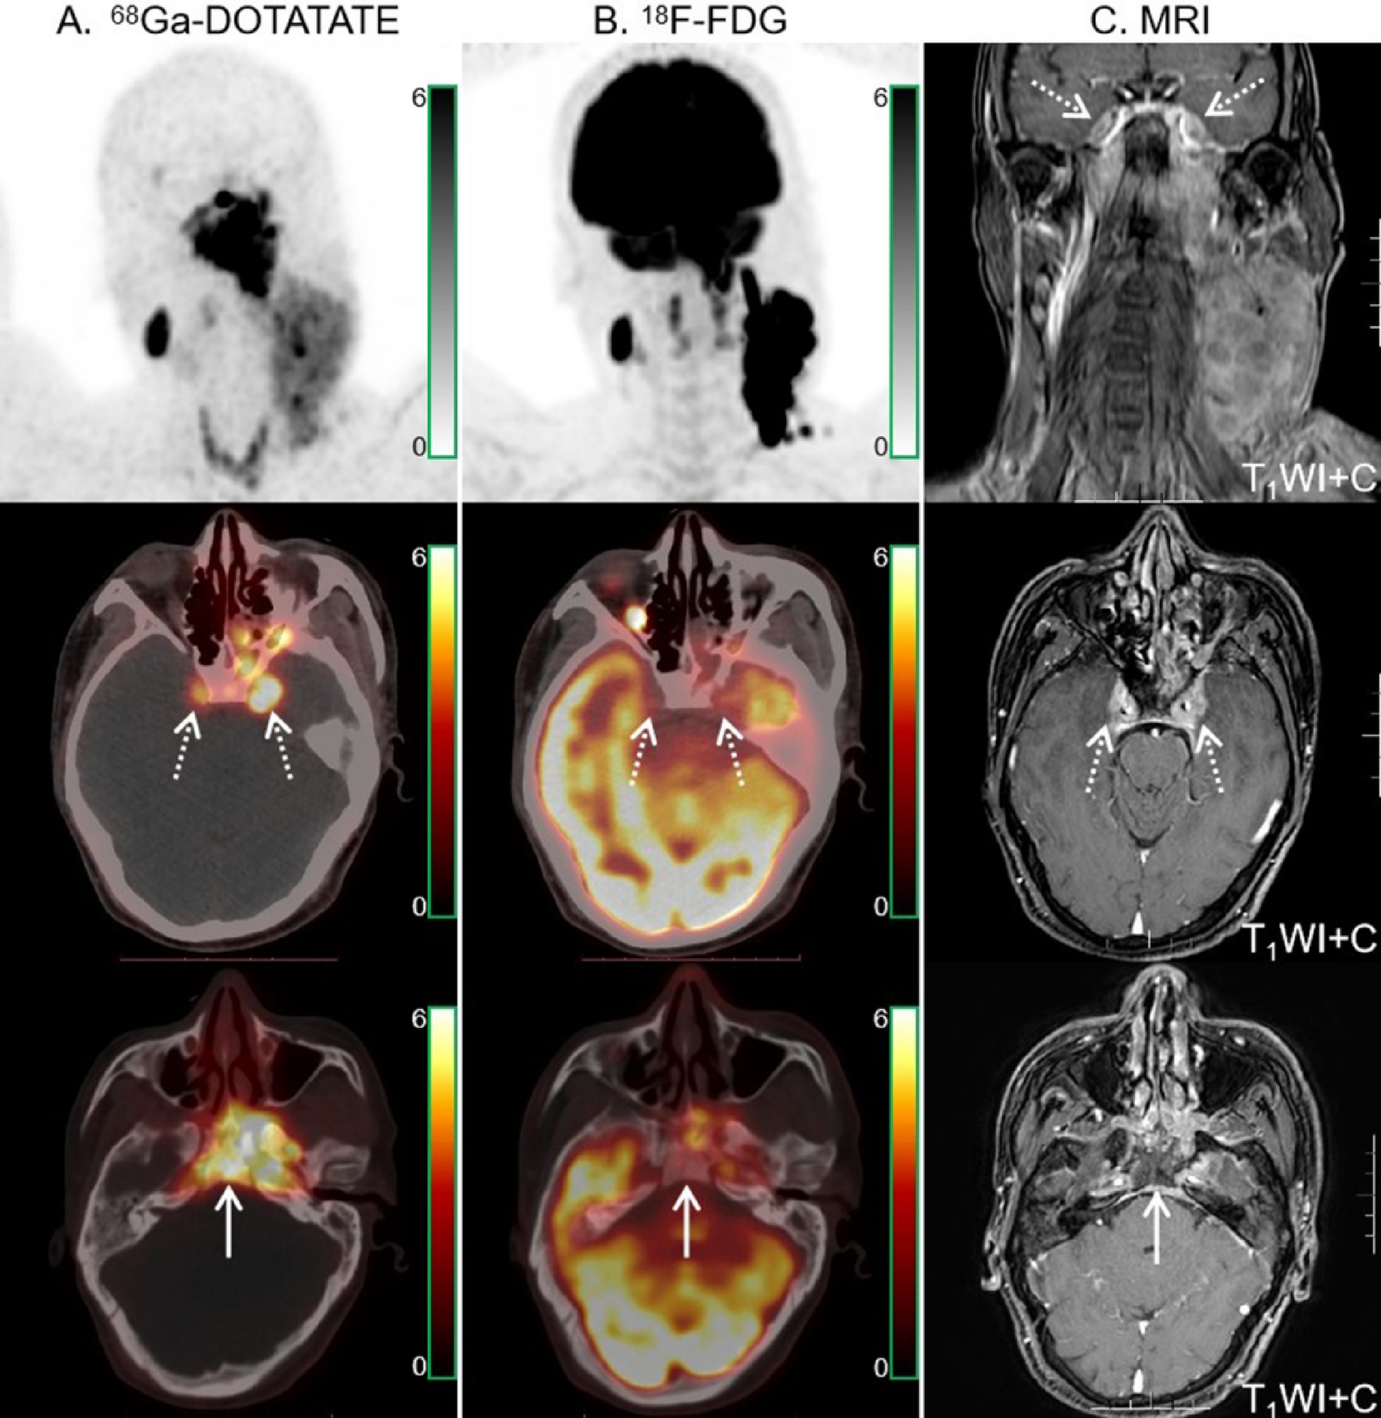

Fig. 3

68Ga-DOTATATE (A) and 18F-FDG PET/CT (B) images in a 43-year-old man with NPC. Intense 68Ga-DOTATATE uptake was observed in the bilateral cavernous sinuses (dotted arrows), suggesting intracranial invasion, but 18F-FDG PET/CT revealed no abnormal intracranial 18F-FDG uptake (dotted arrows). Moreover, 68Ga-DOTATATE PET/CT showed strong tracer uptake in the sphenoid, occipital and petrous bones (solid arrow). The extent of skull base bone invasion (solid arrows) shown by 18F-FDG PET/CT was significantly smaller than that shown by 68Ga-DOTATATE PET/CT. MRI (C) findings were matched with 68Ga-DOTATATE PET/CT.